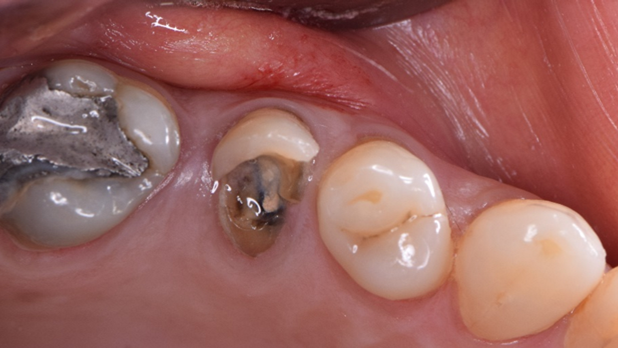

Clinical case: Immediate implant placement using R2GATE Guide & custom healing abutment

- Courtesy of Dr. Sam Omar, Egypt -

Keywords

Dr. Sam Omar, Digital Guided Surgery, Digital ONE-DAY Implant, Maxillary Posterior, #16, Guided surgery, Loading, Flapless, AnyRidge, R2GATE, MEGA ISQ, R2GATE Full surgical kit